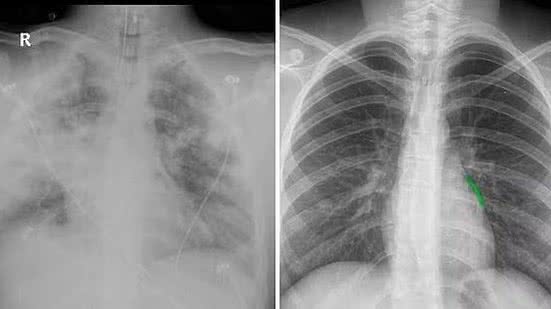

Do lado esquerdo, imagem do pulmão de Diego todo comprometido. Do lado direito, a imagem de um pulmão saudável | Divulgação

O relato é de Lia Paiva, mulher do ex-jogador Serginho e mãe de Diego Paiva dos Santos, de 20 anos. O jovem morreu em 7 de agosto após um infarto pulmonar. Conhecido também como embolia pulmonar, a condição atrapalha a passagem de sangue do coração para o pulmão, comprometendo a oxigenação e podendo levar ao óbito.

"Em quatro dias, o fígado melhorou, o rim melhorou. O antibiótico estava fazendo efeito em todas as partes comprometidas, inclusive no coração. Mas faltava o pulmão. E aí viram que um pulmão já tinha ido e, na madrugada, ele teve o infarto pulmonar no outro pulmão e veio a óbito".

Ela usou a imagem de um pulmão saudável (acima, esquerda, com tons mais escuros) para comparar com o pulmão do filho (acima, na direita, imagem esbranquiçada). "Ele nem pulmão tinha de tanta infecção".

A mãe diz que o vape contribuiu para a morte do filho.

"A causa maior foi a bactéria, mas o pulmão não reagiu pelo uso excessivo do vape".